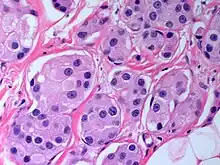

The microscopic histopathology of PACB tumors prepared with hematoxylin and eosin staining shows that >90% of the tumors consist of apocrine gland-like tissue. The lesions must also show that tumor cells have broken through their ducts of origin to invade adjacent tissue in at least one area. Most of the tumor cells (termed type A cells[15]) typically appear somewhat more irregular than normal apocrine gland cells. They have abundant eosinophilic (i.e. pink due to the uptake of the eosin dye) cytoplasm which contain numerous granules[11] and large mitochondria.[15] Their nuclei are large, variably sized and shaped, have multiple nucleoli (which are eosinophilic[11] and may be distinctively large in size[14]), and are surrounded by highly visible nuclear membranes. The cells are arranged into solid sheets, nests, papillae, and/or cords (see Figs. 1 and 2).[11] The tumor cells' cytoplasmic granules test positive when treated with the PAS diastase stain.[16] Binucleated cells, i.e. cells with two nuclei, are common.[10] Less commonly, type B apocrine cells are present; these cells have a more foamy and vacuolated cytoplasm (i.e. containing multiple vacuoles) than type A cells[15] and often resemble foamy histiocytes or sebaceous gland cells.[17] The tumor cells have low to moderate rates of proliferation based on their Ki-67 protein levels.[7] PACB tissues may have localized areas that contain mucin-like secretions within their luminal ducts,[10] localized areas of necrosis (i.e. foci containing dead or dying cells), and/or microcalcifications spotted throughout the apocrine tissue.[11] The stroma (i.e. connective tissue between the sheets, nests, papilla and cords of cells) typically contains non-malignant, infiltrating lymphocytes (see Fig. 3). In an examination of 41 PABC tumors, 33 (80.5%) had <50% of their stroma tissues infiltrated with these cells while 8 (19.5%) had ≥50% of their stroma tissues infiltrated with them. Tumors with ≥50% of their stroma infiltrated with lymphocytes tended to have carcinoma cells that had high rates of proliferation.[11] Metastatic and recurrent PACB tumors have a histopathology similar to their original primary tumors.[14]